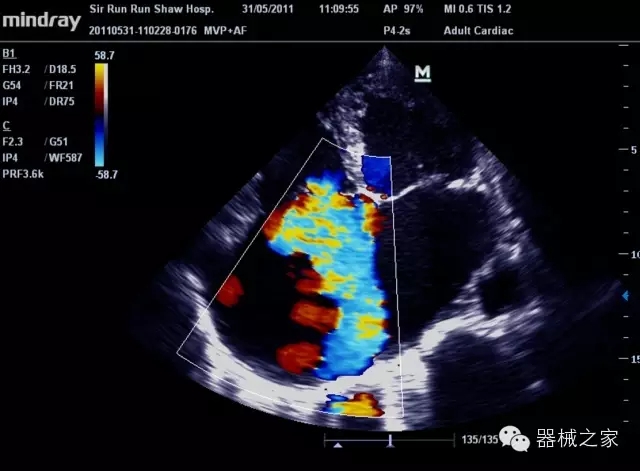

經(jīng)典產(chǎn)品:M7(星鉆)

臨床圖片賞析

產(chǎn)品特點

·裝載有采用Multi-Core多核處理的非嵌入式平臺,成像效率大大提高,并且能夠給用戶帶來高速、多任務(wù)并行信號處理體驗;

·優(yōu)秀的圖像效果、強大的功能體驗、豐富的探頭選擇、合理的便攜式設(shè)計,全中文顯示及病人管理界面,使得M7在任何場合、任何時候都能快速響應(yīng)更好的心血管、腹部、婦產(chǎn)、小器官等常規(guī)超聲檢查以及肌骨、神經(jīng)、顱腦、術(shù)中等新興領(lǐng)域的使用需求;

8倍波束并行處理系統(tǒng)

·在便攜式緊湊平臺上采用更多倍波束并行接收信號處理模式,無論二維還是彩色血流圖像狀態(tài)下,擁有更靈敏的回波頻移捕獲能力,大大提高時間分辨率,尤其使得心血管表現(xiàn)更為突出;